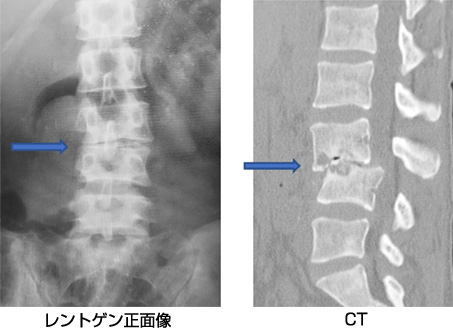

a3f1e84f-s.jpg。骨粗鬆症性椎体骨折に対する脊柱再建術 | 成尾整形外科病院。胸椎・腰椎の疾患 | 聖マリアンナ医科大学 横浜市西部病院。【送料込】 砕米24キロ 割れた米 飼料米 くず米 エサ米 鳥の餌。